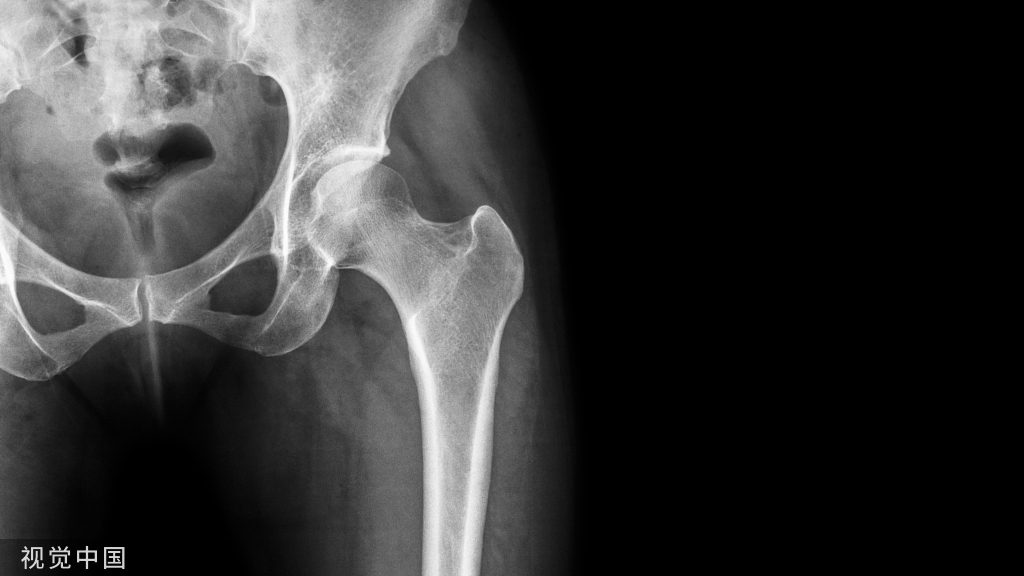

骶骨成形术手术操作:透视下将13G穿刺针置入骶后孔和骶髂关节中间的骶骨翼,与骶髂关节成45度,侧位上位于骶骨正中,一侧可以置入2-3根穿刺针,以保证骨水泥分布均匀,注入骨水泥时正位片上观察,避免骨水泥向内侧延伸,如下图所示。手术操作较胸腰椎椎体成形容易。